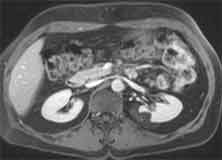

| Zystennieren | Angiomyolipom li. Niere | Hufeisenniere mit Stauung links |